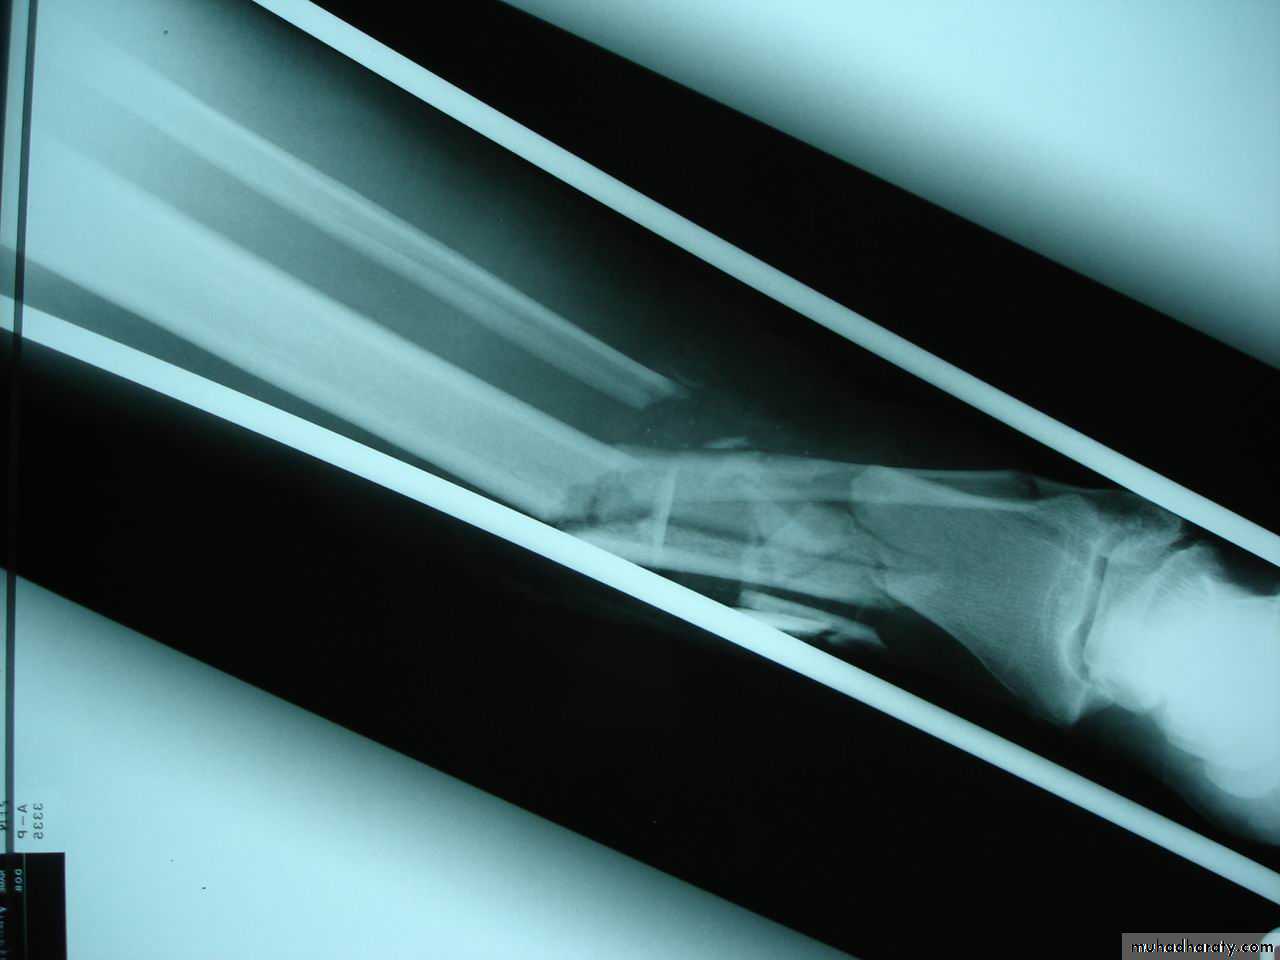

Open (compound) fracture

There is communication between the # and the exterior (disruption of skin, intestine)

↑ Risk of infection